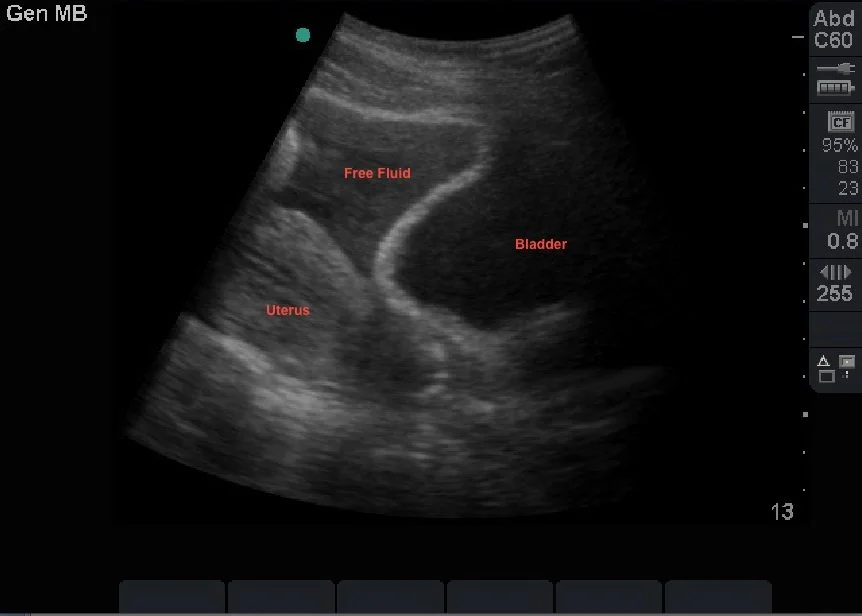

• POCUS can be super helpful here. It would be reasonable to start with a FAST to assess for free fluid. Also take a look at her uterus to assess for evidence of pregnancy, and her ovaries for cysts or ectopic pregnancy

Uh-Oh. Your FAST exam is positive for free fluid around the bladder and in the RUQ.

https://med.emory.edu/departments/emergencymedicine/sections/ultrasound/case-of-the month/trauma/fluid_in_the_pelvix.html